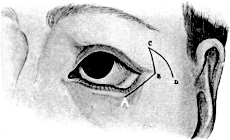

| 315. | Incisions for Lateral Rhinotomy (Moure’s Operation) | 619 |